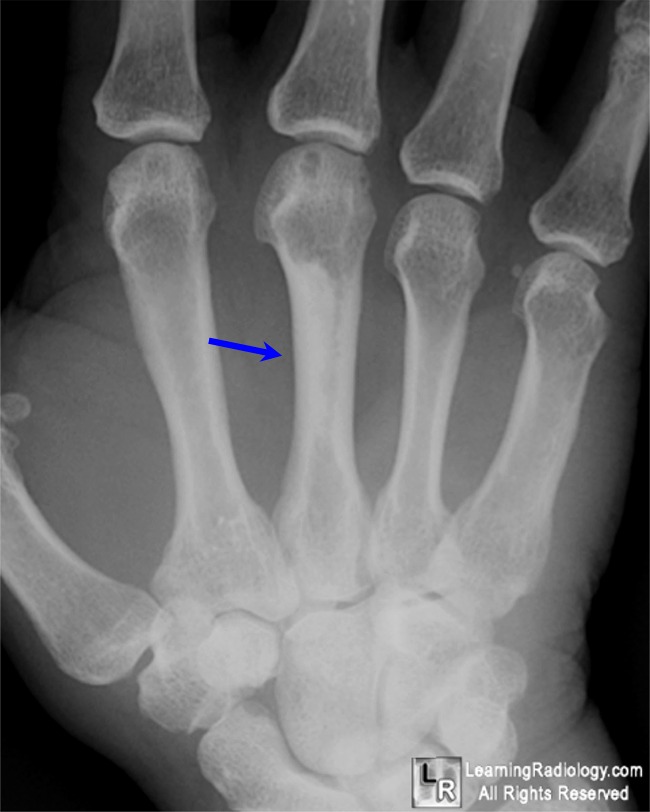

From www.learningradiology.com

LearningRadiology Candle Wax Dripping Sign Tuberous Sclerosis Melorheostosis is a rare benign bone disease including dysostosis and sclerosis. Dripping candle wax sign, also known as flowing candle wax appearance, describes the appearance of sclerotic cortical thickening in. Dripping candle wax presence is a common and typical sign of melorheostosis. Dripping candle wax presence is a common and typical sign of melorheostosis. Dripping candle wax presence is a. Candle Wax Dripping Sign Tuberous Sclerosis.

LearningRadiology Candle Wax Dripping Sign Tuberous Sclerosis Dripping candle wax presence is a common and typical sign of melorheostosis. Dripping candle wax sign, also known as flowing candle wax appearance, describes the appearance of sclerotic cortical thickening in. Melorheostosis is a rare benign bone disease including dysostosis and sclerosis. This sign appears as irregular hyperostosis of the cortical bone which is likened to melted wax flowing down. Candle Wax Dripping Sign Tuberous Sclerosis.